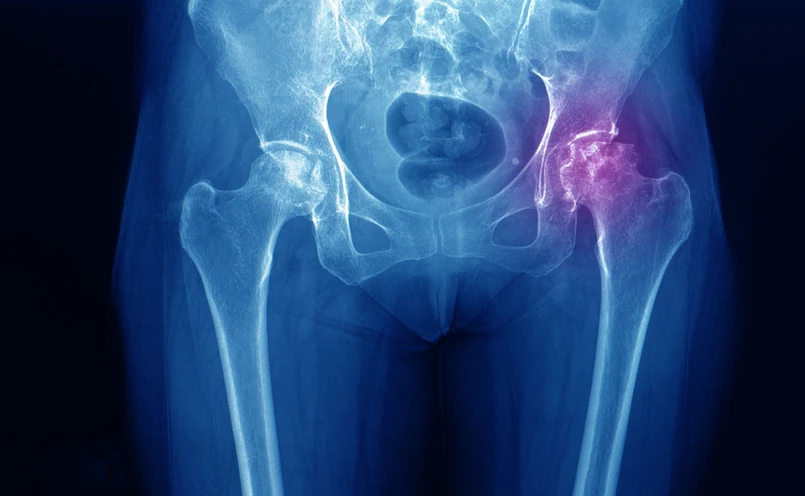

Kość udowa, miednica

shutterstock

Występujące najczęściej u osób starszych i wymagające długotrwałego leczenia złamanie szyjki kości udowej pozostaje globalnym problemem dla zdrowia publicznego. Osoby z takimi złamaniami są zależne od otoczenia, często dochodzi u nich do potencjalnie groźnych dla życia powikłań. Złamania te są dużym obciążeniem nie tylko dla pacjentów, ale również ich rodzin i systemu opieki zdrowotnej.